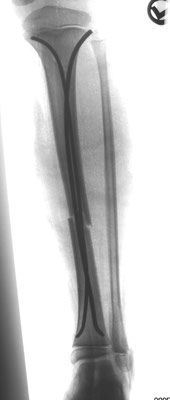

14- jähriger Junge mit Unterschenkelbruch. Minimal-invasive Stabilisierung mit Markdrähten. Das Bein kann bei optimaler Anwendung der Drähte bereits nach einer Woche mit 15 kg an Gehstützen belastet werden.

Stark verschobener Unterschenkelbruch bei einem 14- jährigen. Minimal-invasive Stabilisierung mit winkelstabiler Platte. Das Bein kann nach Abklingen der akuten Schwellung bereits wieder mit 15 kg an Gehstützen belastet werden. Volle Belastbarkeit nach 6 – 10 Wochen.